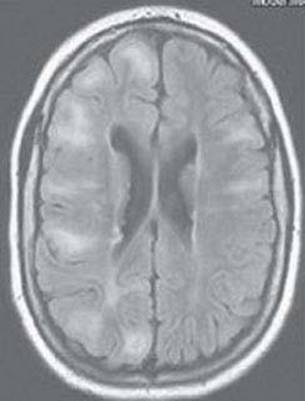

97. A 15-year-old boy with growth and psychomotor retardation, sensorineural hearing loss, frequent headaches, and seizures presents for evaluation of multiple stroke-like episodes. Two MRIs from different time points are shown in Figure 14.23. Lactate level is found to be elevated. Which of the following is the most likely diagnosis?

FIGURE 14.23 Axial DWI MRI from two different time points

b. Mitochondrial encephalopathy, lactic acidosis, and strokes